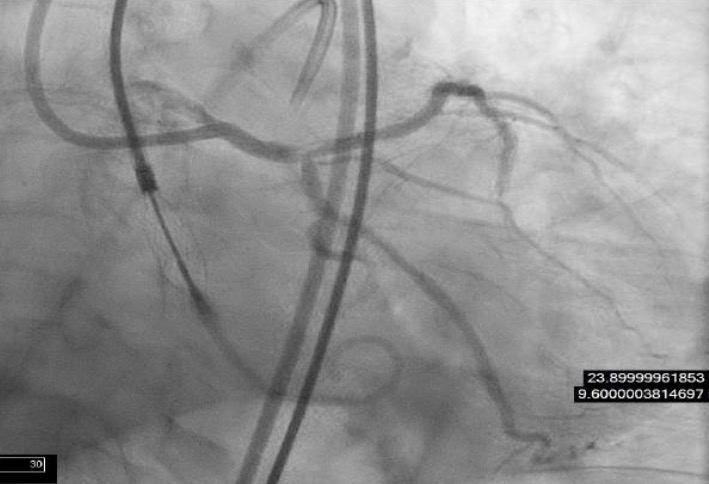

First Successful Use Of 2 Axial Flow Catheters For Percutaneous Biventricular Circulatory Support As A Bridge To A Durable Left Ventricular Assist Device Circulation Heart Failure